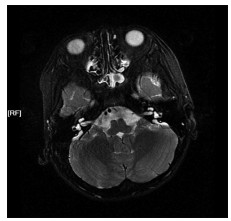

分析2024年8月就诊于温州医科大学附属第一医院儿童神经内科的1例肌张力减退-共济失调-发育迟缓综合征(hypotonia-ataxia-developmental delay syndrome,HADDS)患儿的临床表型及遗传学病因,患儿为1岁2个月,因“发育迟缓半年余”就诊。临床表现为肌张力减退、全面发育迟缓、异常面部特征及共济失调等。家系全外显子组测序发现患儿EBF3基因存在c.1038C>A(p.Y346*)无义变异,Sanger测序验证父母均无此变异。经分析,依据美国医学遗传学与基因组学学会标准,该变异被判定为致病性。通过复习文献总结相关疾病临床表现与遗传学特征,该病例不仅扩展了EBF3变异所致HADDS的变异谱,还丰富了其临床表型,为该疾病研究提供了新的案例与依据。